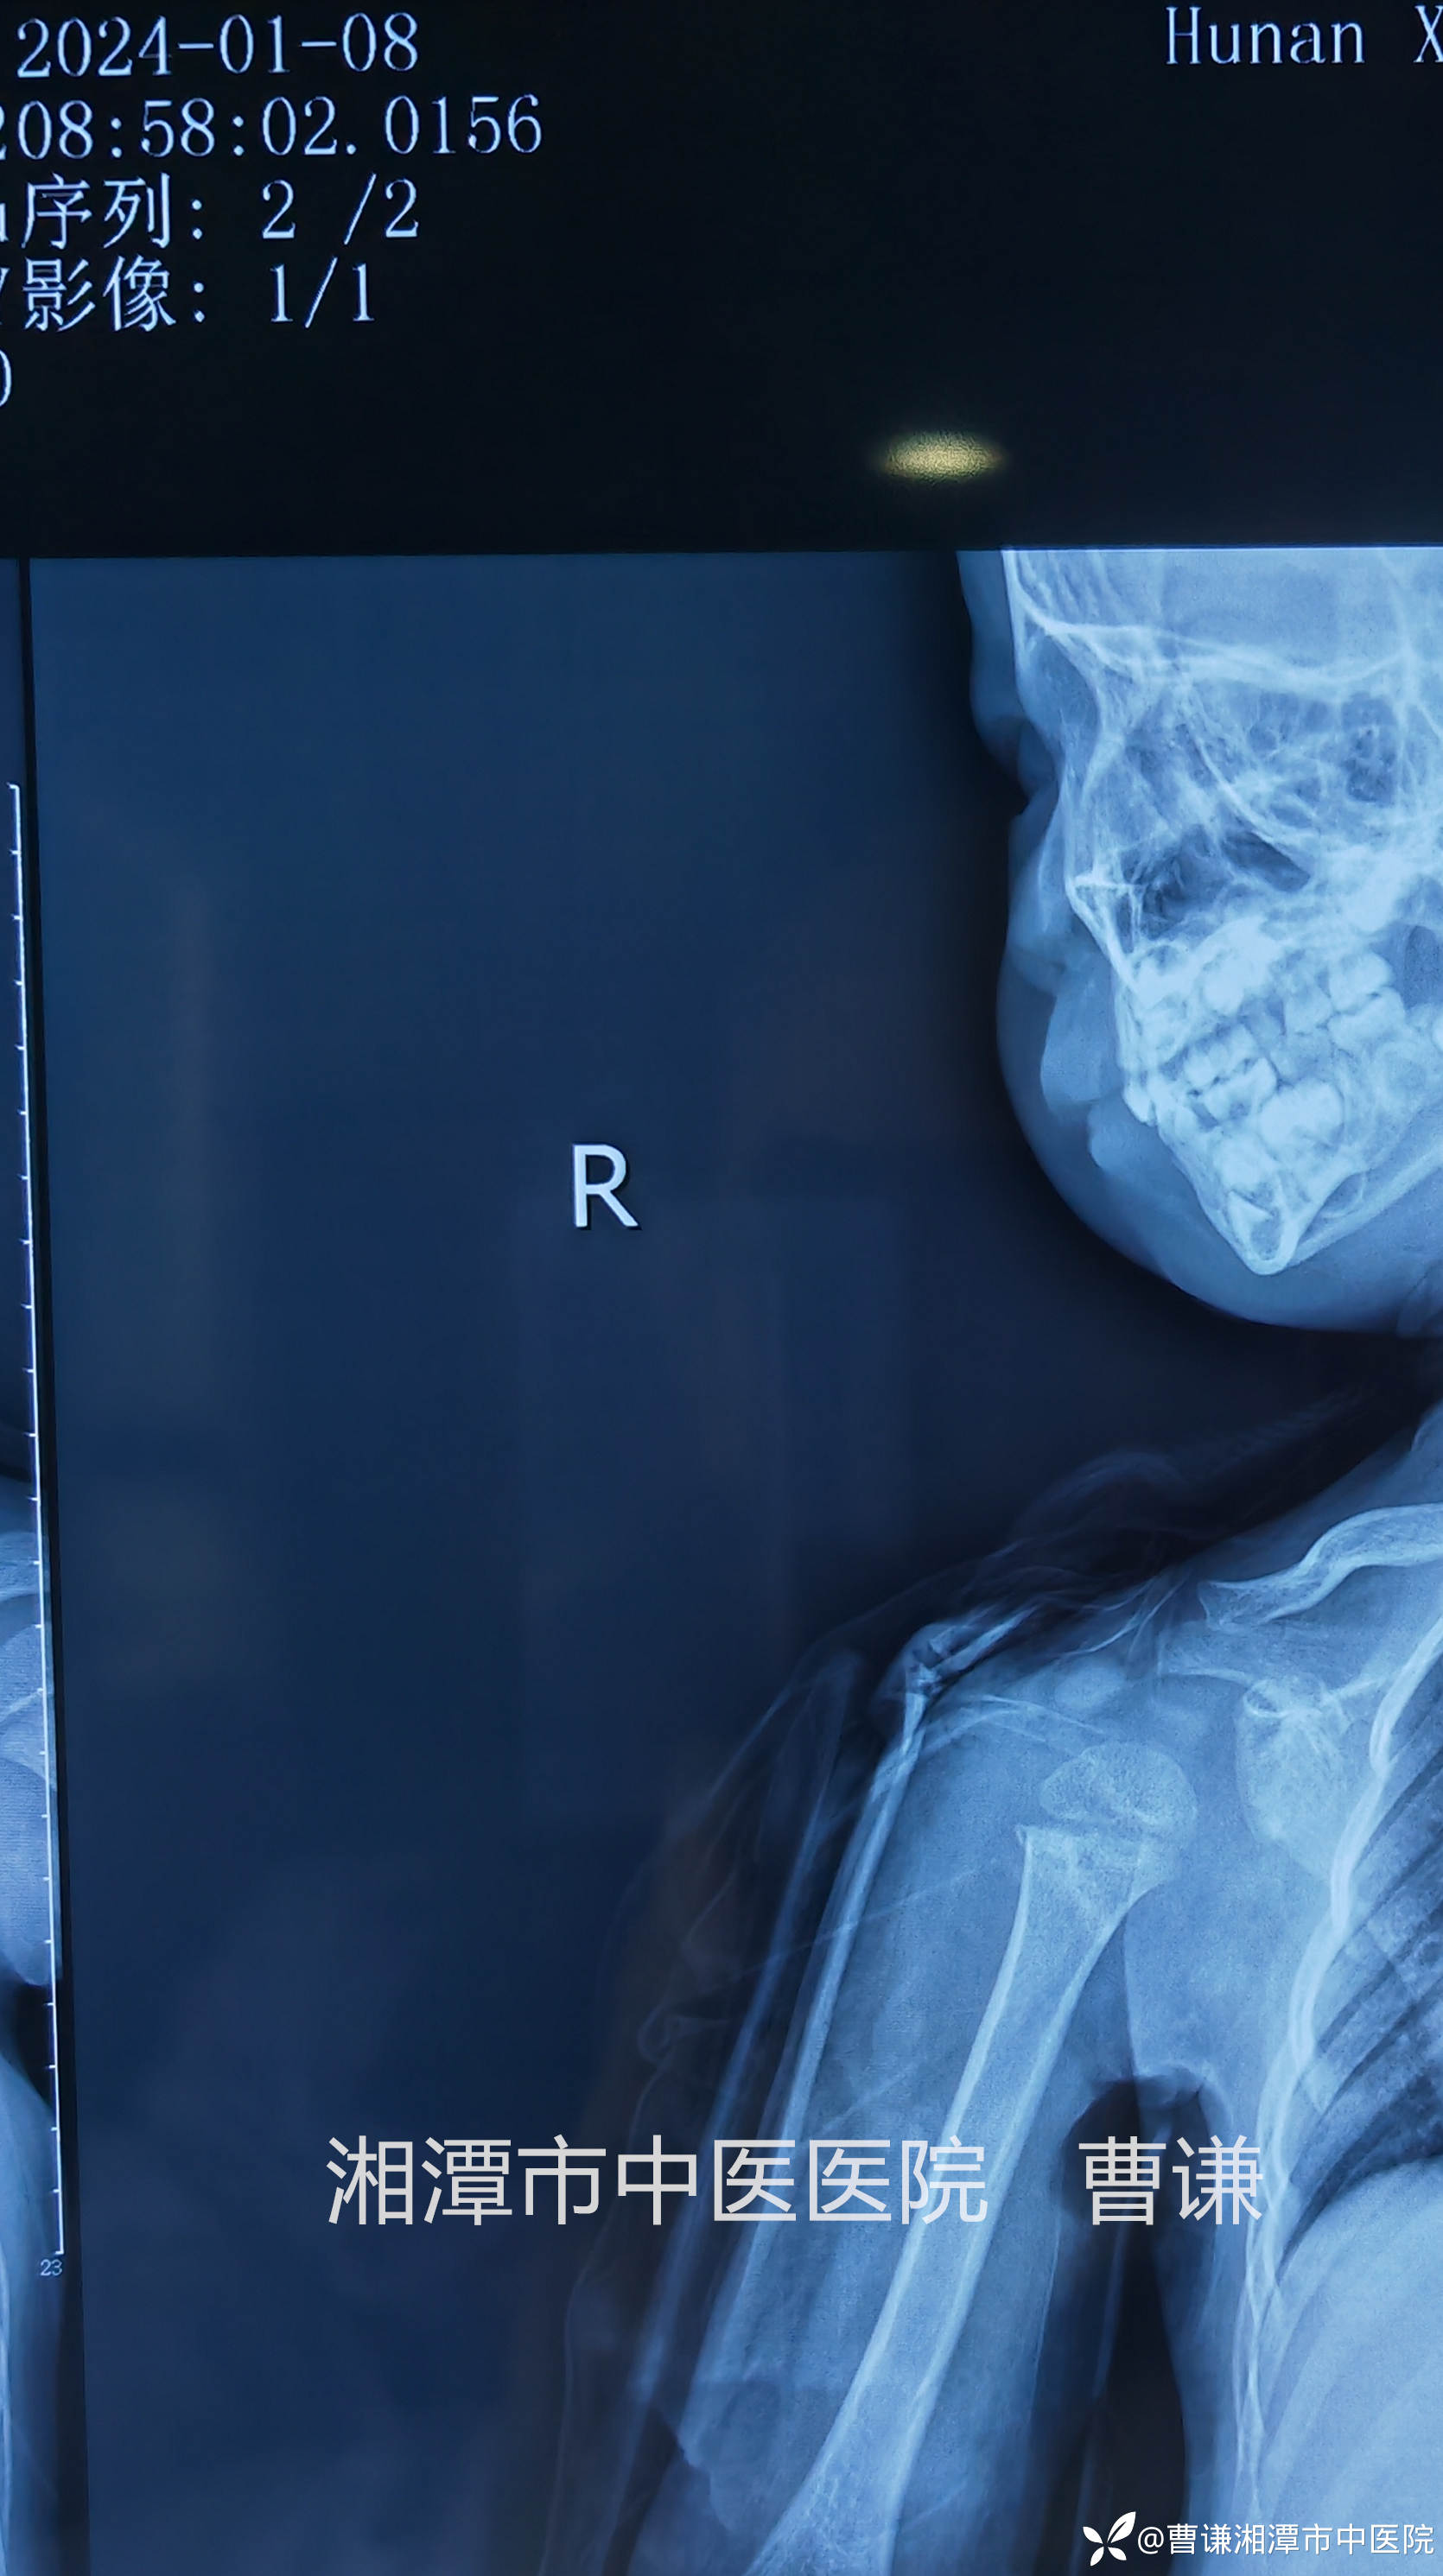

辅助检查:X线片:右肱骨近端骨折,断端错位明显。

患者跌倒致右肩部肿痛,活动受限,就诊于当地医院,拍片示右肱骨近端骨折,初看片子似乎骨折对位良好,其实仔细看可以发现断端重叠明显,虽然拍了两个片子,但其实都是正位,当地医院建议手术治疗,患者家属拒绝手术治疗,转来我院要求保守治疗。

当地医院予以石膏固定转来我院,来我院拍片复查示:远折端向前、向内、向上移位明显,石膏固定显然是无效的,因为患者夜间一直诉疼痛,良好的外固定应该是可以让患者基本无痛的。